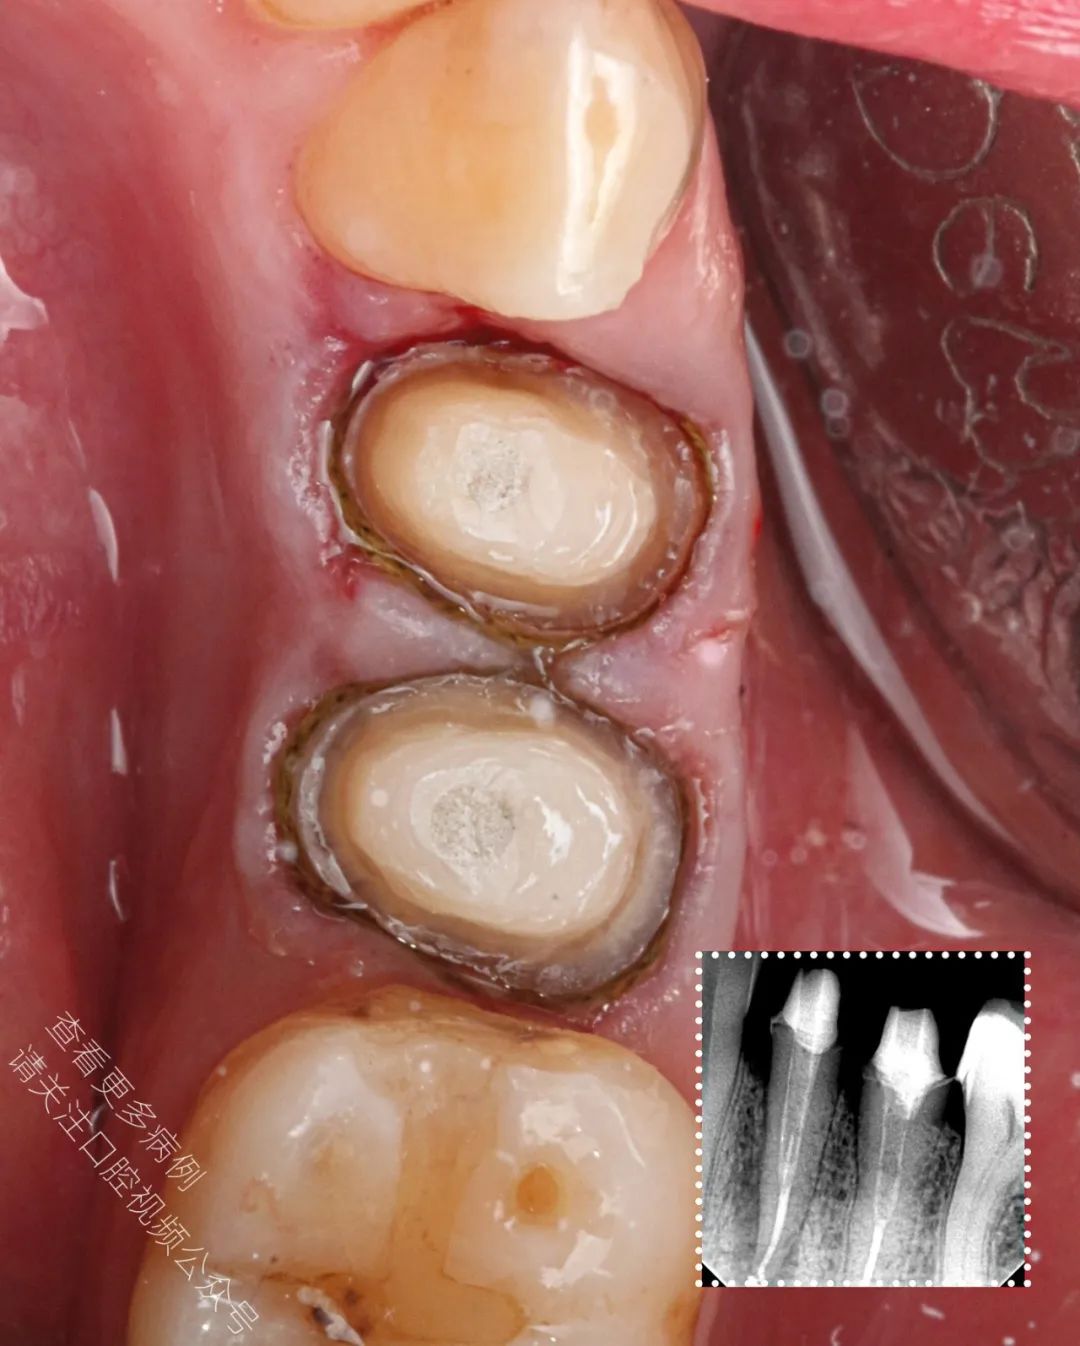

🪄 成功使用橡皮障隔离,对两颗前磨牙进行了再根管治疗(ReRCT)

🪄 使用纤维桩进行核修复(也可选择嵌体冠 endocrown 作为替代方案)

🪄 放置排龈线后进行数字化取模,为制作 e.max 全瓷冠做准备